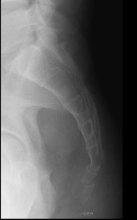

Bij aanhoudende klachten wordt nog vaak een laterale X foto geadviseerd zowel in zit als in stand om te zien hoe de positie is van het stuitje.

Klachten uiten zich met name in pijnprovocatie bij (langdurig) zitten of opkomen uit zit. De diagnose wordt gesteld middels de anamnese waaruit deze klachten blijken en het opwekken van de pijn bij palpatie of mobilisatie van de coccyx.